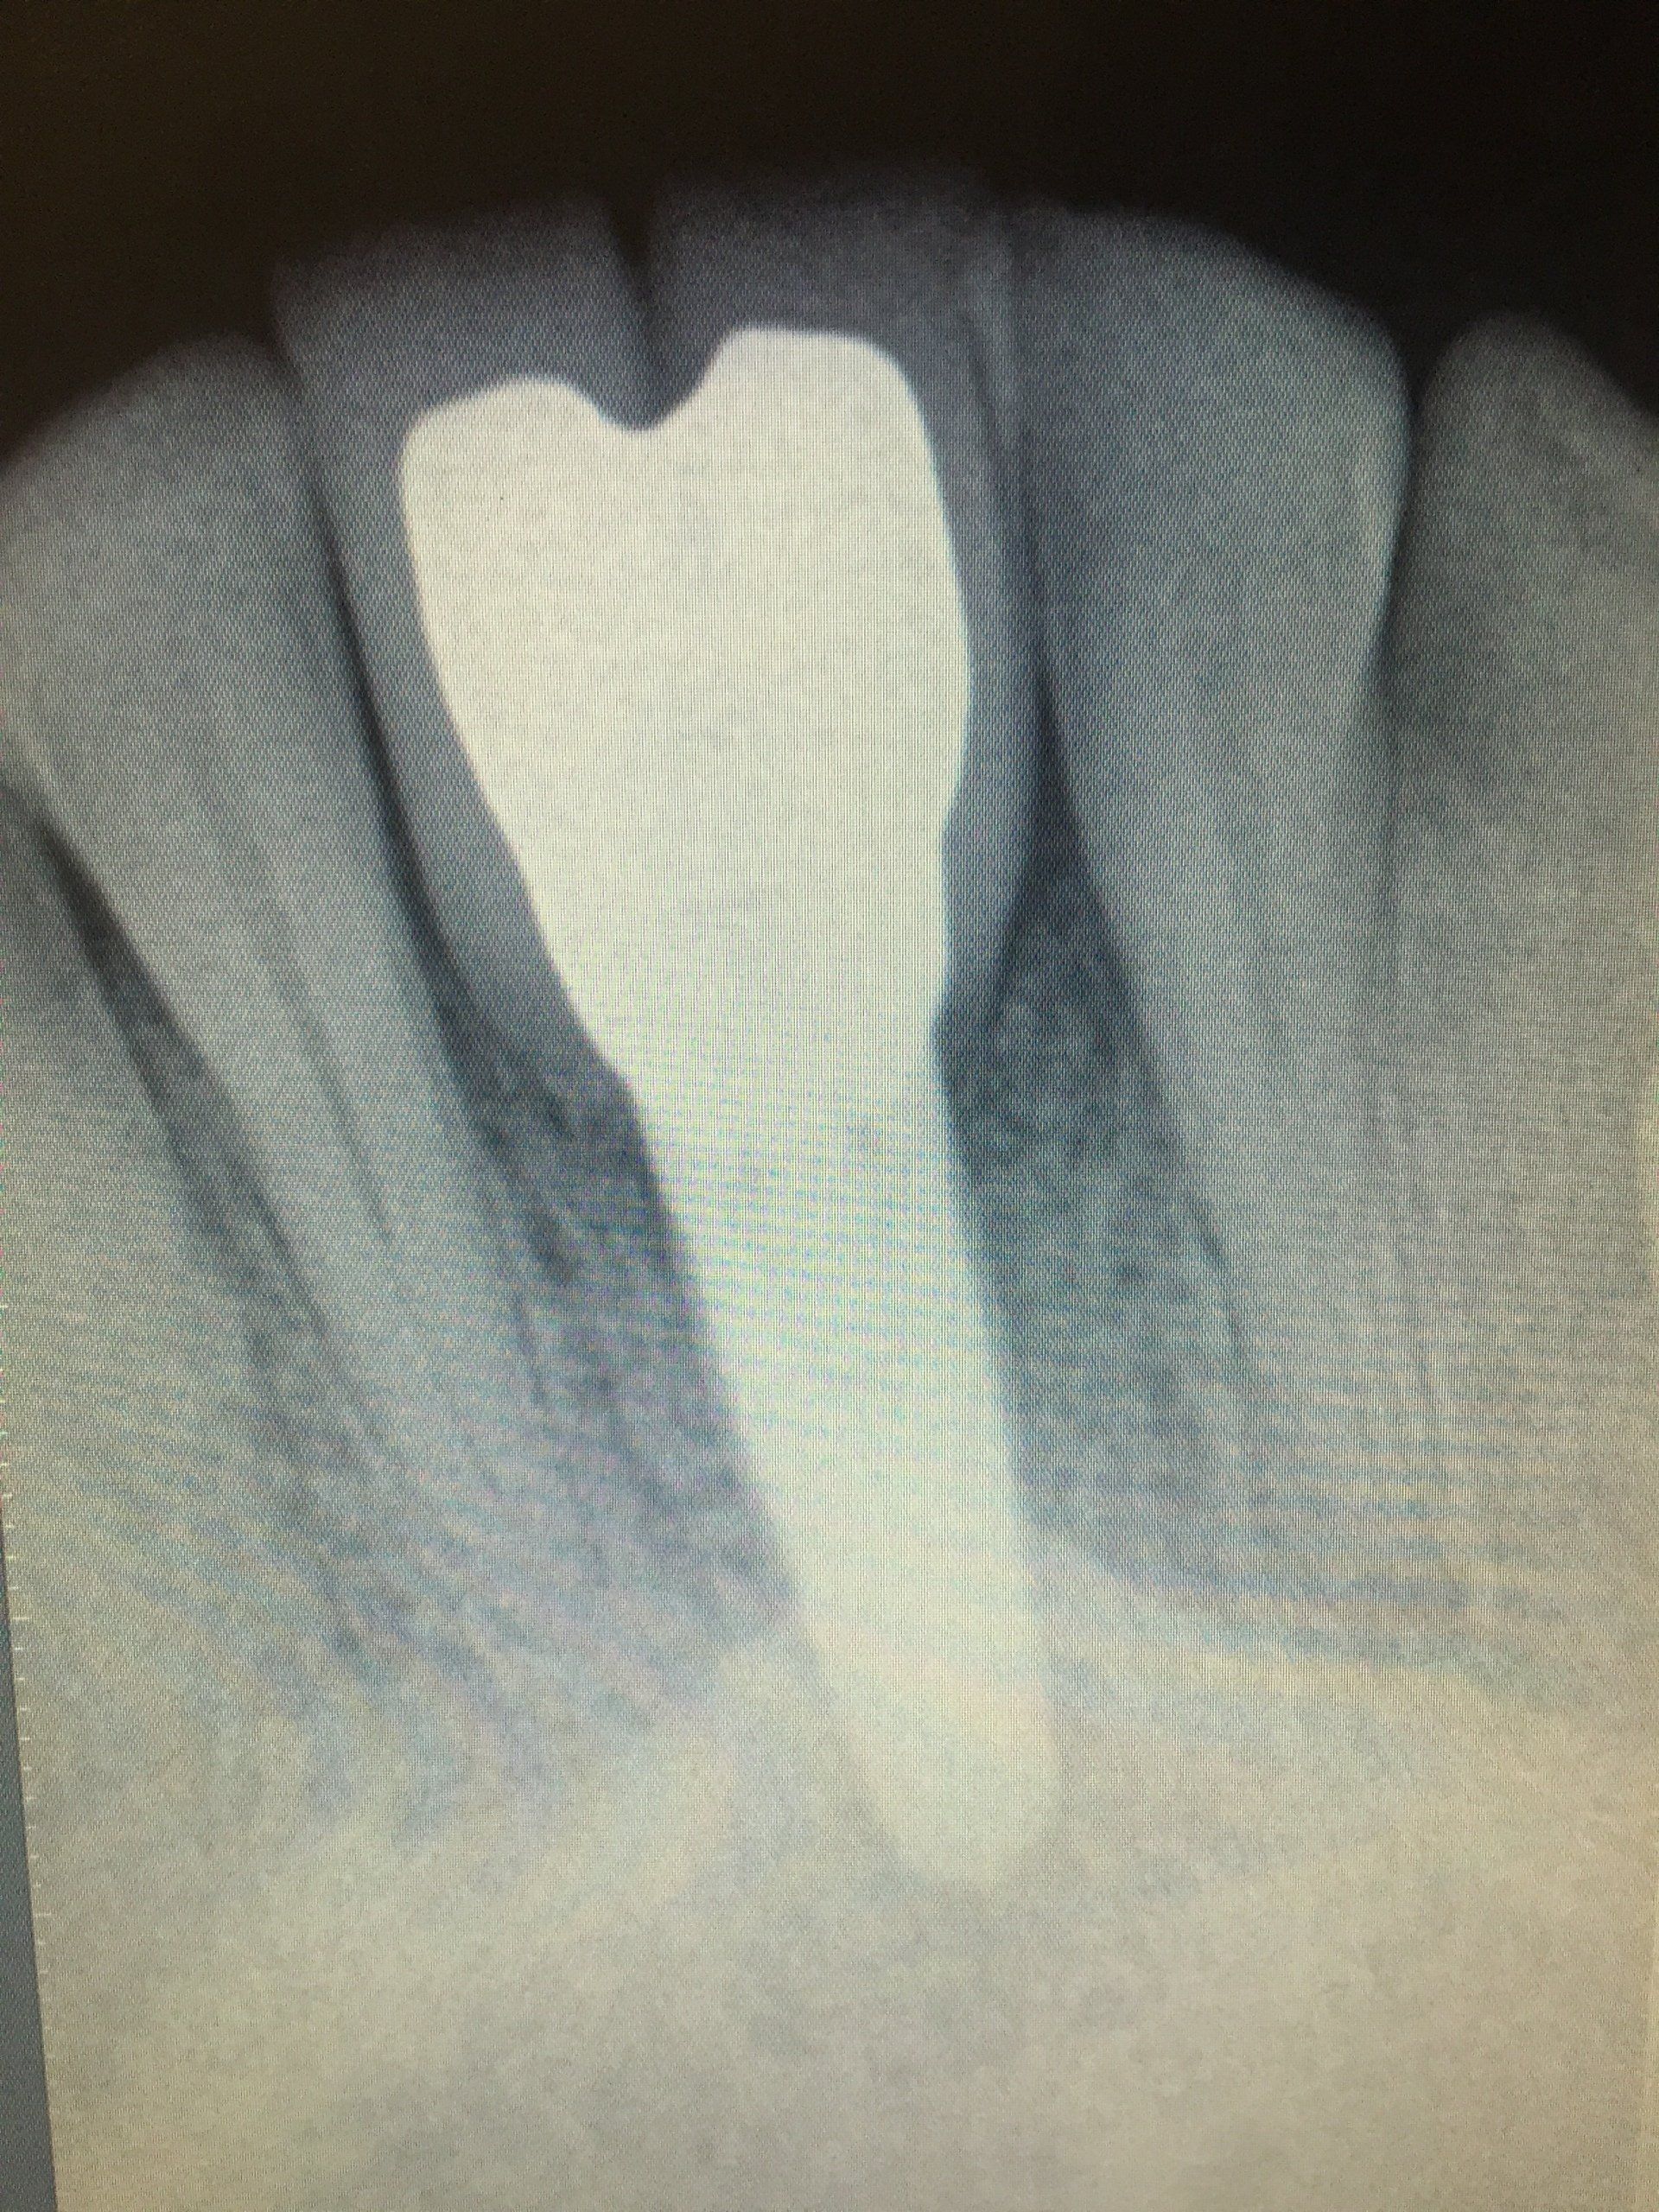

Gallery

A healthy and radiant smile is the goal. We offer dental care and

information on how you can prevent any diseases.